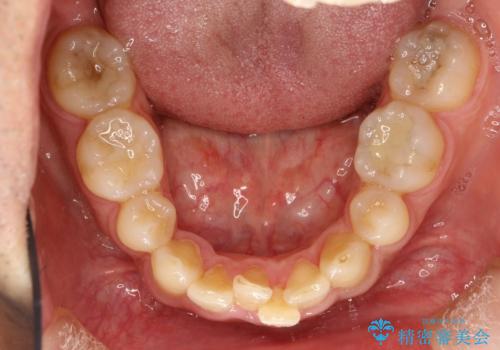

- 以前、上下左右4本抜いてワイヤー矯正をしていた方で、後戻りで下の前歯のガタガタを気にして来院されました。

マウスピース矯正にて、下の歯はIPR(歯と歯の間を削る)を入れることでガタガタの改善、咬み合わせの深さも改善をはかる治療計画をたてました。

歯と歯の間を削って隙間を作って矯正をしています。